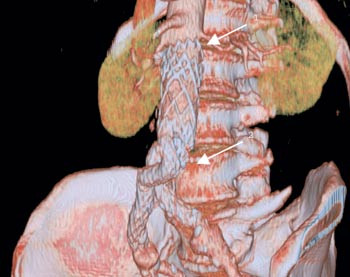

De komplikasjoner som knytter seg til behandlingen, kan inndeles i tidlige og sene. De tidlige knytter seg i stor grad til selve innsettelsen av protesen, hvor de anatomiske forhold er av vesentlig betydning. De sene komplikasjonene er forårsaket av stentgraftenes begrensede stabilitet, holdbarhet og aortasykdommens fortsatte utvikling med utvidelse av aneurismehalsen og bekkenarteriene, forskyvning av protesen når aneurismet skrumper eller at graftbeina glir opp i aneurismesekken (fig 2, 3). Dermed oppstår det lekkasje ut i aneurismesekken, som utsettes for systemtrykk på nytt. En del av disse komplikasjonene kan unngås med spesiallagede stentgrafter, suprarenal fiksering, embolisering av lumbalarterier, aa. iliacae internae samt god forankring i bekkenarterier. Med økt erfaring kan man også lettere skille ut de av aneurismene som ikke egner seg til stentgraftbehandling. De tidlige problemene er kjent og fører til hyppigere kontroller og behandling såfremt dette er indisert. Hos de pasienter hvor man finner at alt er i orden, tas kun årlige CT-kontroller. Lekkasje og ruptur kan oppstå når som helst imellom disse kontrollene (9, 10), noe som skjedde for to av våre pasienter.

Hos enkelte pasienter oppstår det stadig nye problemer, noe som resulterer i flere reoperasjoner (7, 11). Hvis aneurismediameteren øker og man ikke kan behandle dette endovaskulært, bør pasienten tilbys konvensjonell behandling med fjerning av stentgraftet (12). Dette forutsetter at pasienten tåler åpen kirurgi. I vårt materiale var det ingen dødelighet forbundet fjerning av stentgraftet, verken i elektive tilfeller eller hos pasienter med aneurismeruptur. Flere studier har vist at risikoen ved slike reoperasjoner er økt i forhold til konvensjonell førstegangs aortakirurgi (13) – (15). Man vet i dag at enkelte stentgrafttyper har begrenset holdbarhet og derfor er tatt ut av markedet. Det er flere pasienter som fortsatt lever med disse stentgraftene, og disse trenger derfor hyppige kontroller. Man bør derfor vurdere hvorvidt de årlige CT-kontroller bør suppleres med ultralydundersøkelser et par ganger i året for å identifisere lekkasjer. Ved CT-kontroller bør idenfikasjon av lekkasje og utmåling av aortadiameteren suppleres med inspeksjon av oversiktsbildet, samt tredimensjonale rekonstruksjoner for å avdekke trådruptur og desintegrasjon av proteseskjelettet.